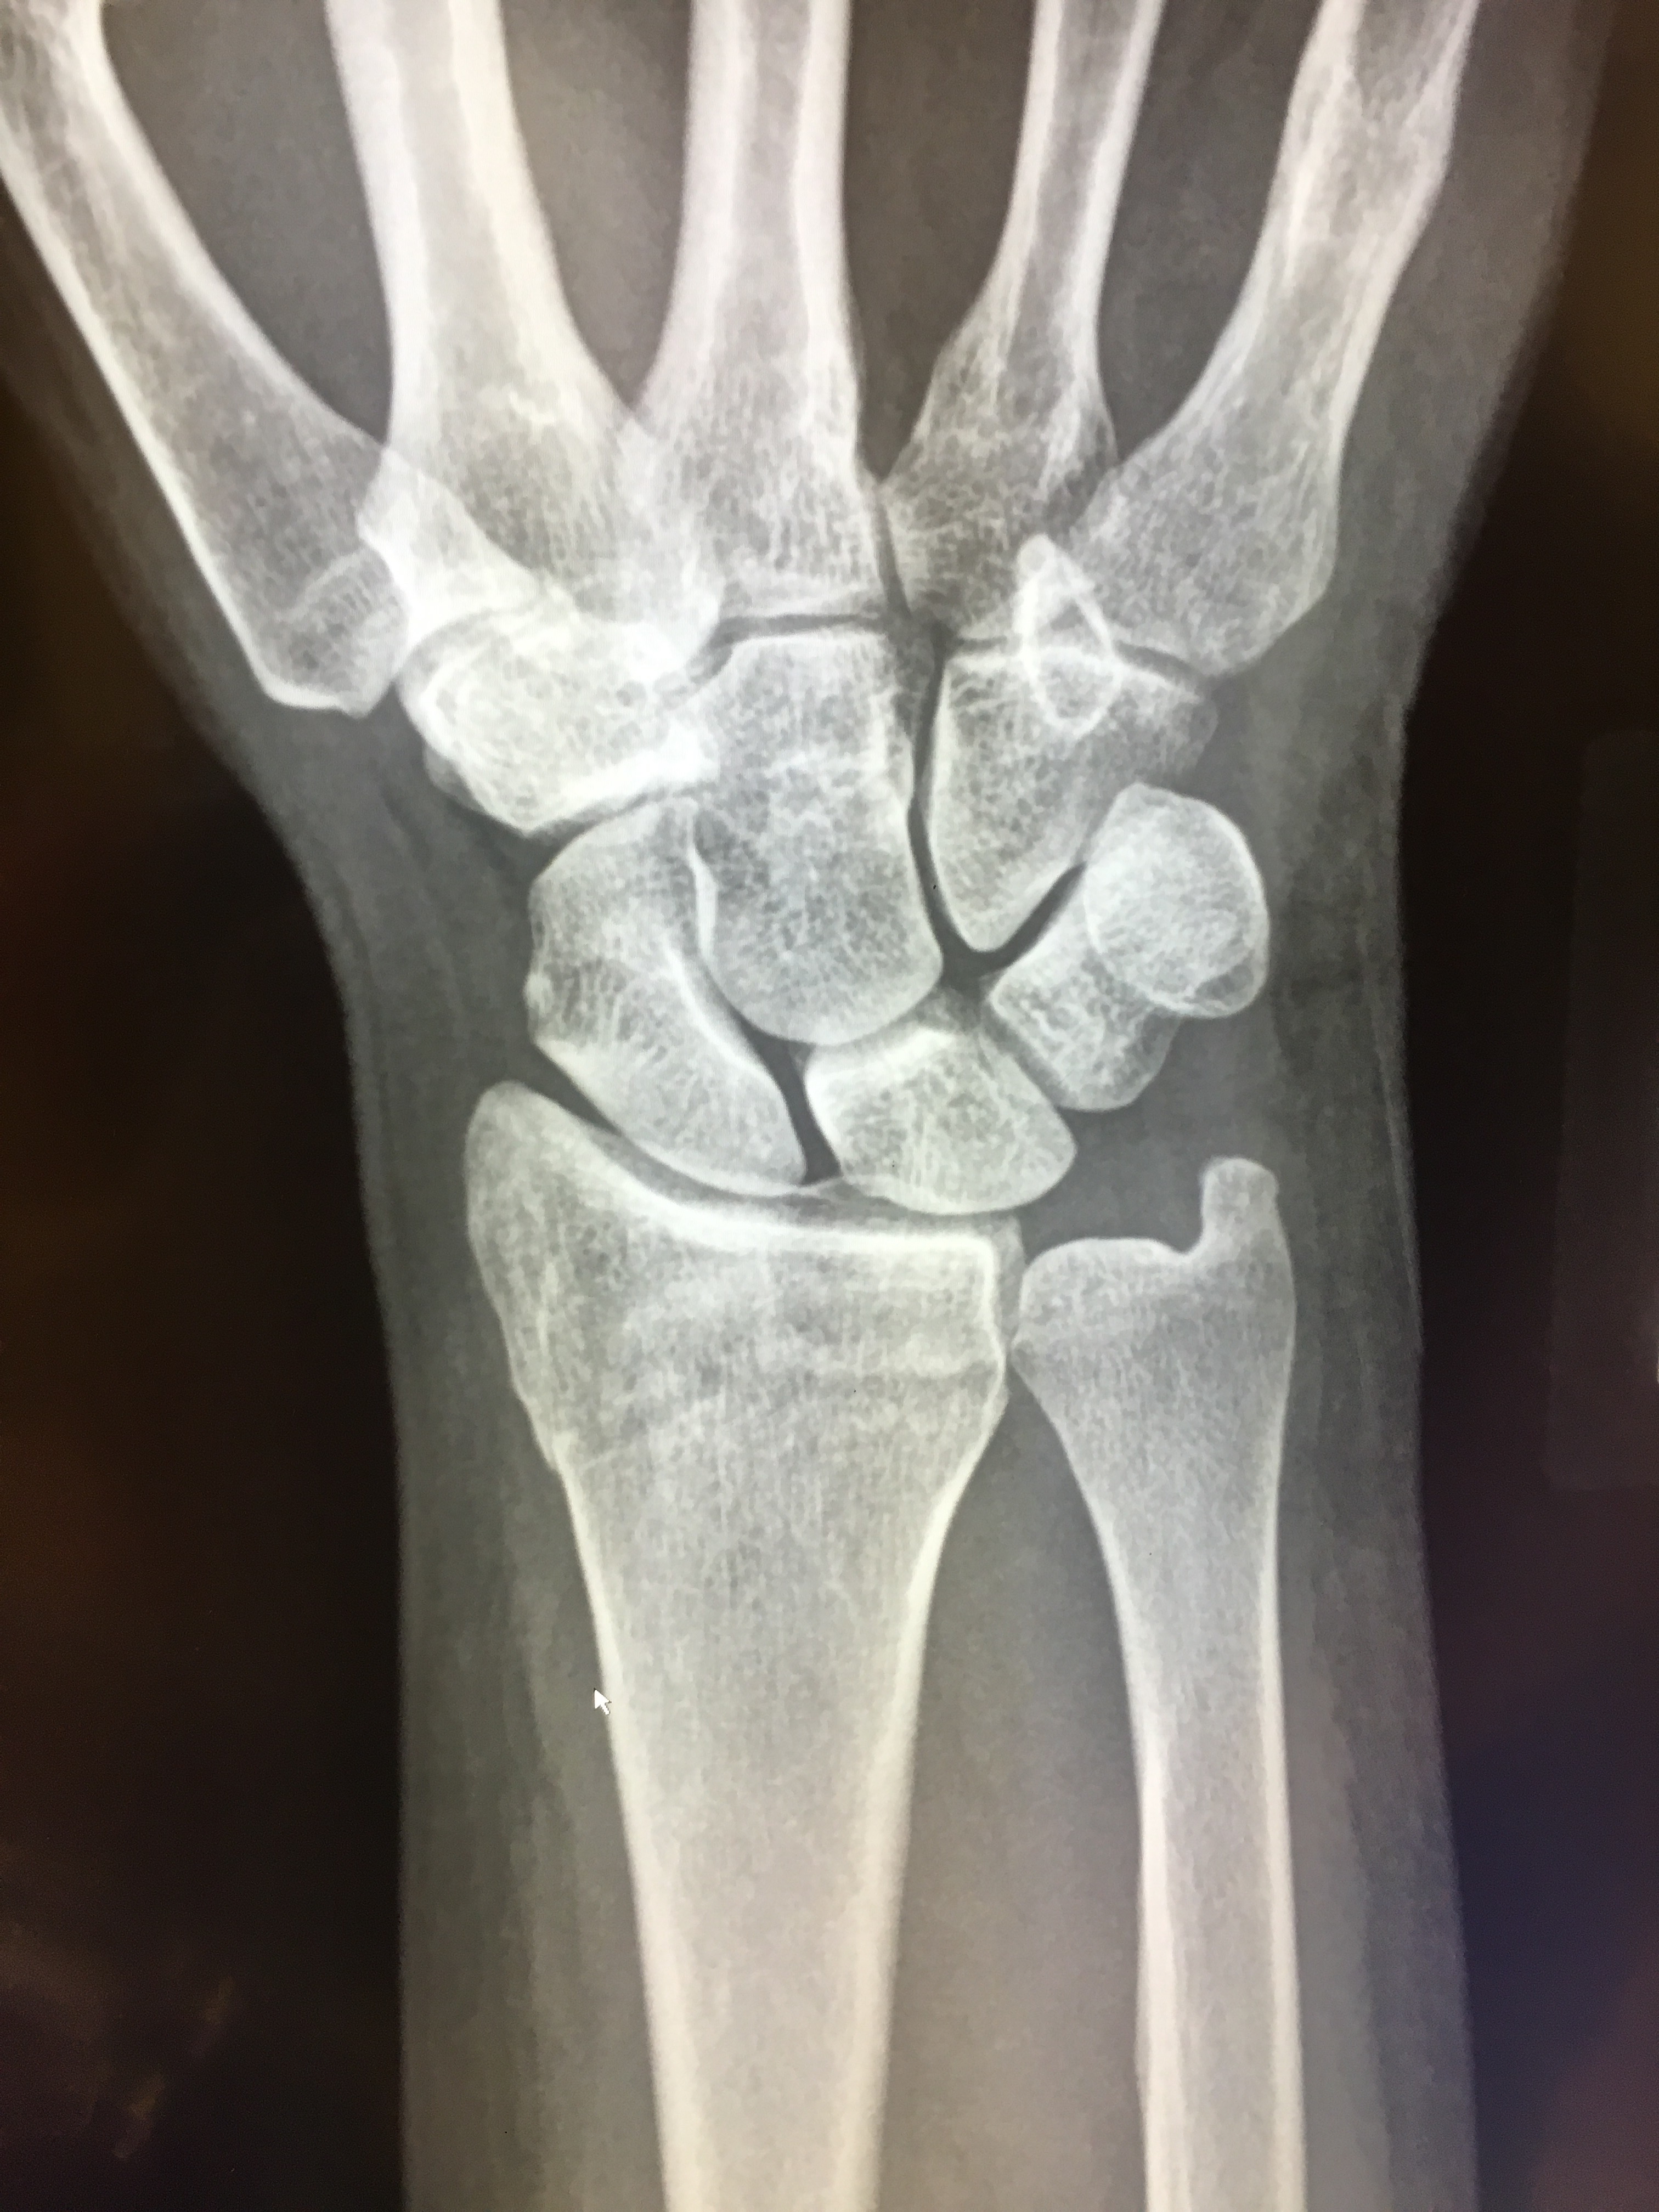

Things have since taken a bit of a sad turn. The orthopedic surgeon wanted to do surgery (today), planning to insert a plate so as to realign the displaced radial bone in my wrist.